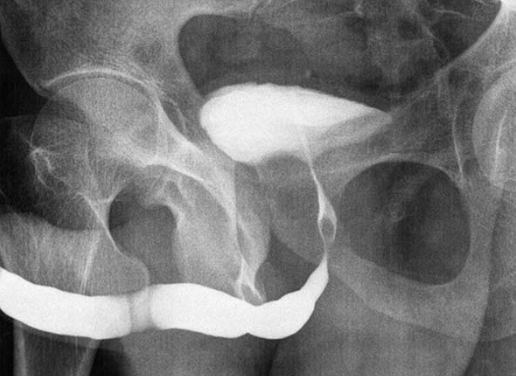

Imagem de Estenose Uretral

Uretrografia mostrando uma estenose severa no segmento da uretra bulbar.